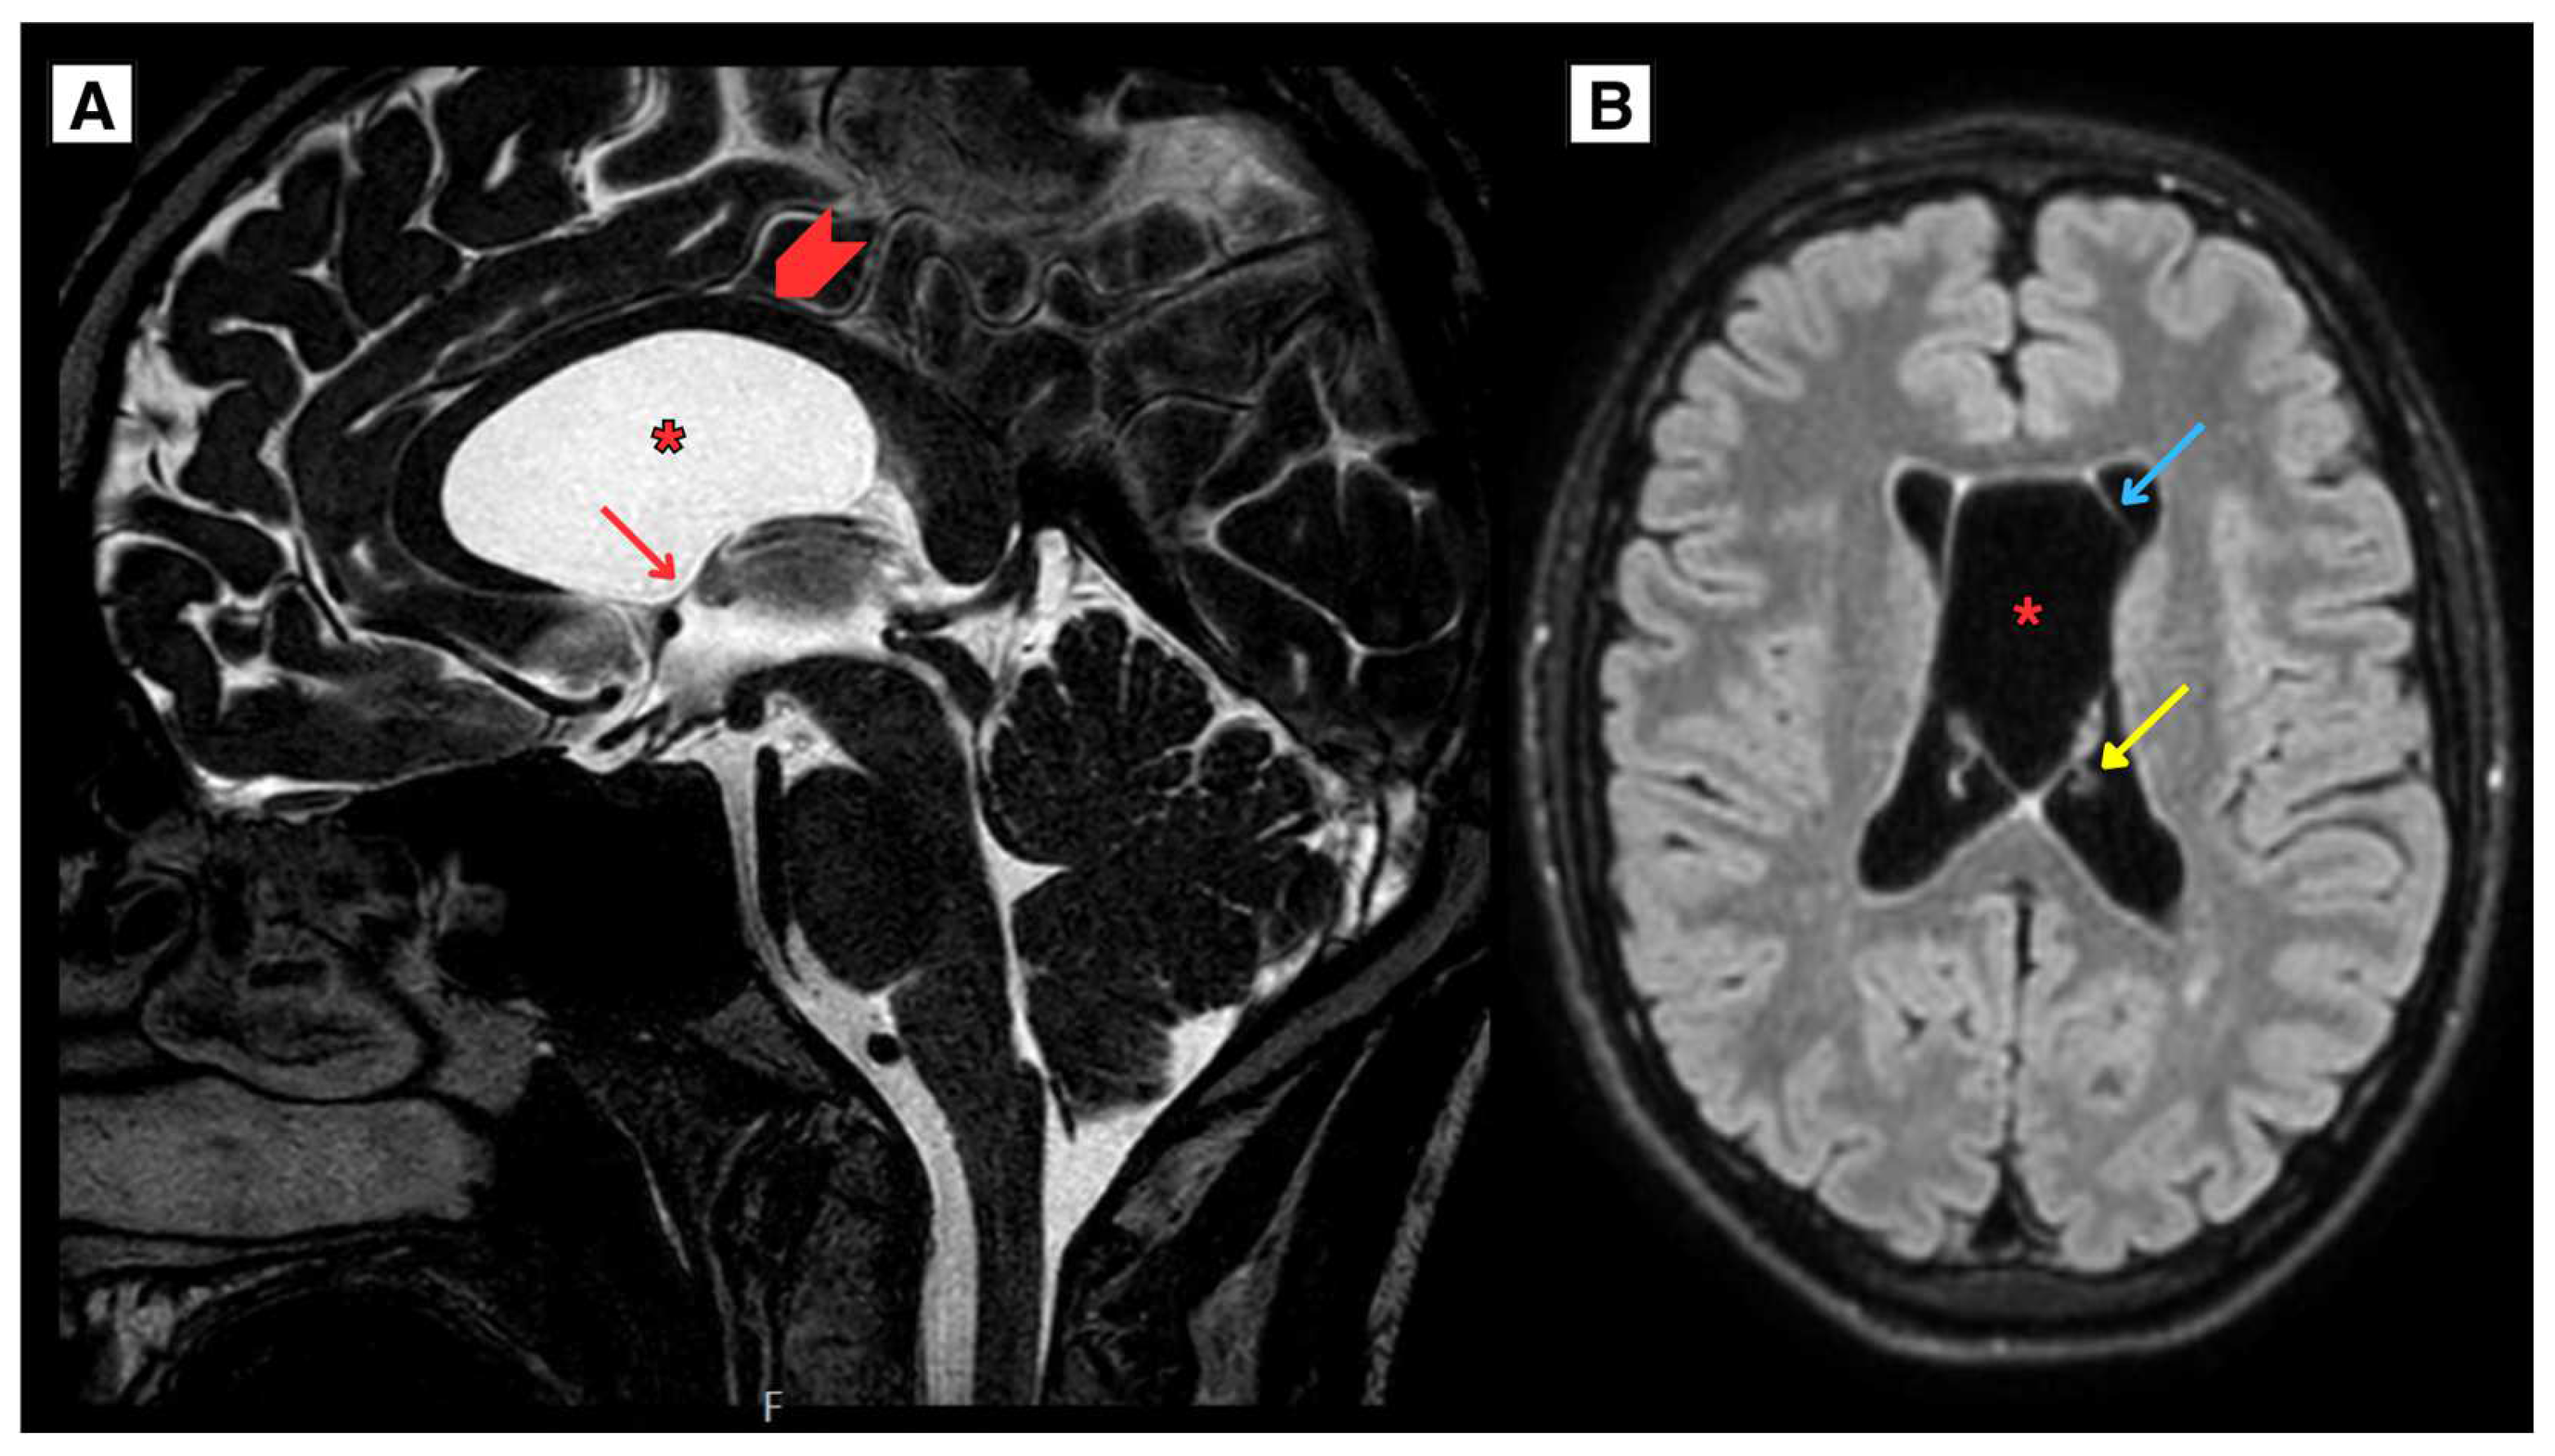

2.1. Retrospective imaging Review

2.2. A Novel Anatomical Pattern in CSP Cyst Imaging